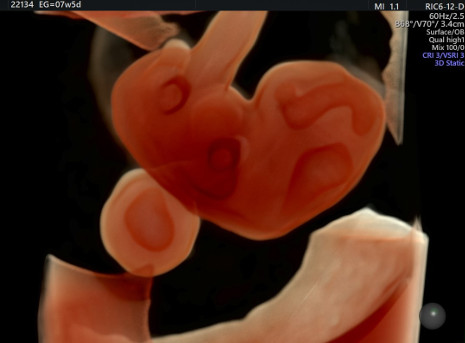

El Hospital El Pilar en colaboración con Clínica Ripoll cuenta con el ecógrafo más preciso para la salud de la mujer. Su capacidad de realizar imágenes multicorte y por transparencia de alta definición ofrece una gran precisión para el diagnóstico tanto fetal como ginecológico

, cuenta con un ecógrafo de última generación Voluson E10 BT18, capaz de ofrecer imágenes de alta definición en 2D, 3D y 4D HD live Silhouette- HD liv estudio desde las primeras semanas de gestación y una excelente penetración para exámenes técnicamente difíciles tanto fetales como ginecológicos.

Diagnóstico prenatal y vínculo materno-filial

"Esta nueva herramienta" afirma el Dr. Ripoll "permite obtener imágenes multicorte como si se tratara de un TAC desde las primeras semanas de embarazo en formato digital, así como poder visualizar enfermedades del feto antes de nacer. Así, cuando detectamos alguna anomalía podemos compartir las imágenes con otros especialistas.

El estudio anatómico fetal se realiza de forma automatizada, descartando el error humano "por ejemplo mediante la mediación automática del pliegue nucal se puede observar si hay un alto riesgo de que el feto tenga síndrome de down" asegura el Dr. Ripoll. Y gracias al Doppler de alta definición que se visualiza en volumen, se puede estudiar el funcionamiento del corazón, el cerebro y detectar si puede haber alguna patología como cardiopatías congénitas o enfermedades neurológicas como una comunicación interventricular en el corazón o una agenesia del cuerpo calloso en el cerebro del feto.

"Además, es importante destacar el factor emocional. Para las futuras madres ver la cara de sus hijos de forma tan definida consigue aumentar el vínculo madre-hijo desde mucho antes del nacimiento".